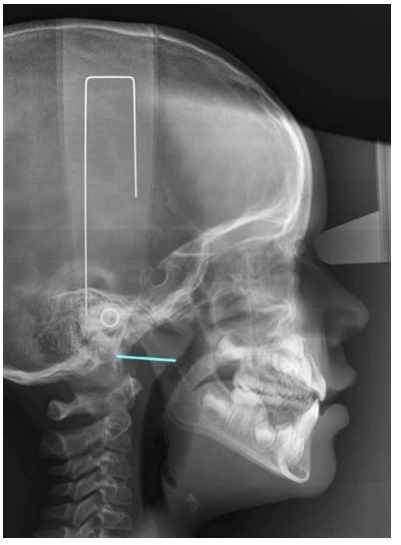

En la actualidad la relación entre oclusión y posturología despierta un gran interés científico, sobre todo de cara a la instauración de un tratamiento multidisciplinar. Sin embargo, la diversidad de estudios se refiere sobre todo a la población adulta y no hay un consenso común entre las diferentes investigaciones. En base a ello nos planteamos como objetivo estudiar la posición craneocervical en diferentes oclusiones en población en desarrollo. Mediante un diseño de carácter transversal fueron seleccionados 64 pacientes pediátricos con historia clínica completa y radiografías laterales de cráneo de calidad. Las variables analizadas mediante el software de ImageJ® y Nemoceph® fueron FP-MP, ángulo ANB, OPT-SN, CVT-SN y Ad1-Ba. El análisis estadístico descriptivo y comparativo se llevó a cabo mediante el programa programa IBM SPSS® hallando posteriormente la fiabilidad intraexaminador. Los valores p obtenidos para cada una de las variables fueron 0,846 para FP-MP, 0,008 para el ángulo ANB, 0,155 para OPT-SN, 0,415 para CVT-SN y 0,221 para Ad1-Ba. Por todo ello, creemos que la posición craneofacial en las diferentes oclusiones podría estar determinada por el hecho de que el desarrollo todavía no ha finalizado.

Currently, the relationship between occlusion and posture arouses great scientific interest, especially during the establishment of a multidisciplinary treatment. However, the diversity of studies refers mostly to the adult population and there is no common agreement among the different investigations. Based on this, we aimed to study the craniocervical position in different occlusions in the developing pediatric population. Through a crosssectional design, 64 pediatric patients with complete clinical history and high-quality lateral skull radiographs were selected. The variables analyzed by ImageJ® and Nemoceph® software’s were FP-MP, ANB angle, OPT-SN, CVT-SN and Ad1-Ba. Descriptive and comparative statistical analysis was carried out with IBM SPSS Statistics® software, subsequently finding intra-examiner agreement. P-values obtained for each of these variables were 0.846 for FP-MP, 0.008 for ANB angle, 0.155 for OPT-SN, 0.415 for CVT-SN, and 0.221 for CVT-SN. Based on these results, we believe that the craniofacial position in the different occlusions could be determined by the fact that the development has not yet been completed.